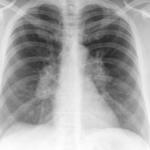

Sarcoid

Album: Sarcoid

Date: 04/20/2004

Size: 63 items

Views: 38756